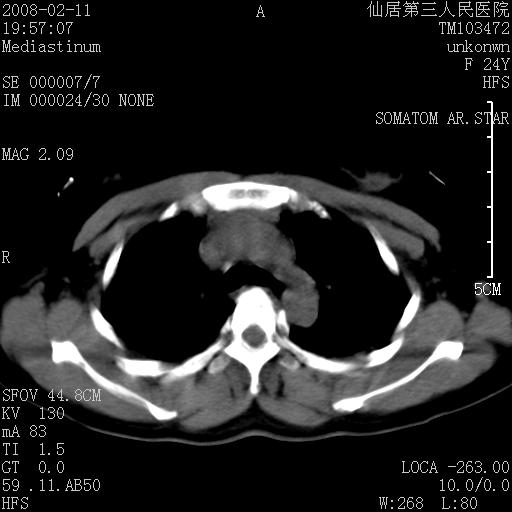

以下是引用zjzjr在2008-2-12 14:32:00的发言:[br]胸腺大点,是不是胸腺瘤或胸腺增生